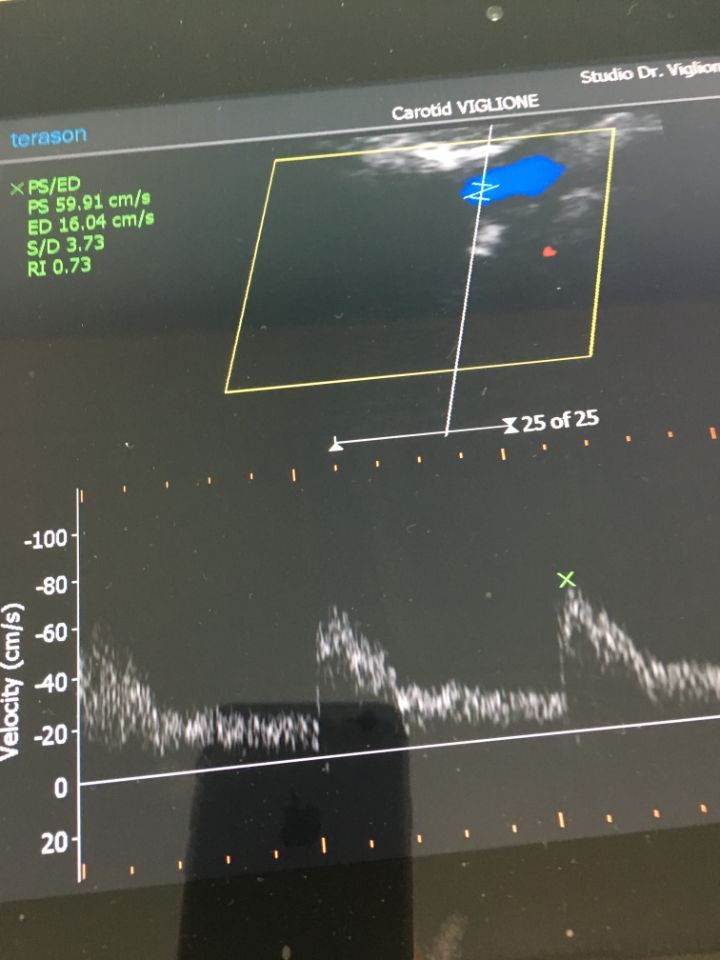

Ecco alcune immagini degli interventi eseguiti dal Dottor Viglione presso il suo studio a Cuneo.